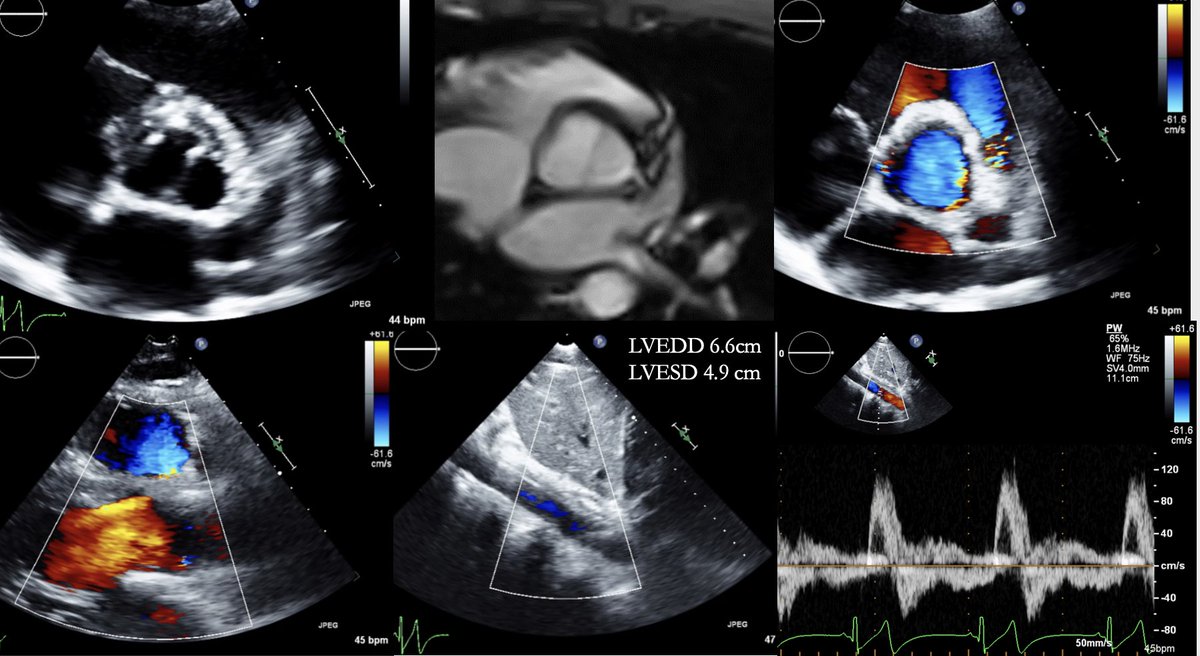

Join us at 8.00am in Oregon 203 to learn how imaging guides management in HCM. #echofirst #ASE360 @mmartinezheart

Key takeaway: ✅Athletic participation doesn’t necessarily accelerate disease progression, it requires careful monitoring ✅Advanced imaging (CTA, MRI, echo) helps us detect risks early and make informed decisions

✅Decisions on surgery/ restrictions aren’t just about heart size—it’s about collaboration, shared decision-making, and tailoring care to each athlete’s needs.